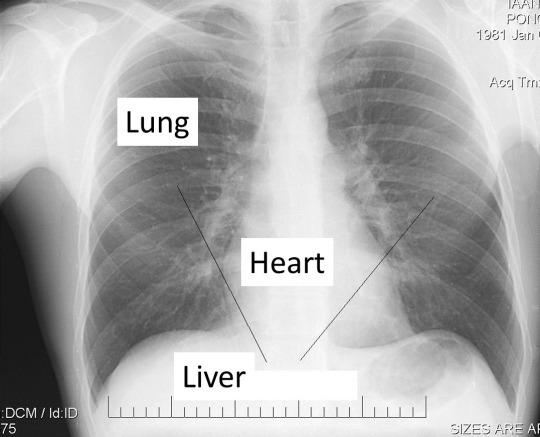

Anatomy of heart and liver

A human heart is located in the middle of a chest, diagonally from right to left.

The liver is under the heart on the right. The heart is covered slightly by the lungs (pink).Male

nipples are at the level of the fifth rib, sometimes, slightly above or

slightly below it. If we draw a line between the nipples, we cross the

heart at its widest part.

found an X-ray of a young male. What can we see on this X-ray? The

white areas are the heart, liver, and bones. The dark areas are lungs.

Let us put this X-ray on Benedict’s chest.